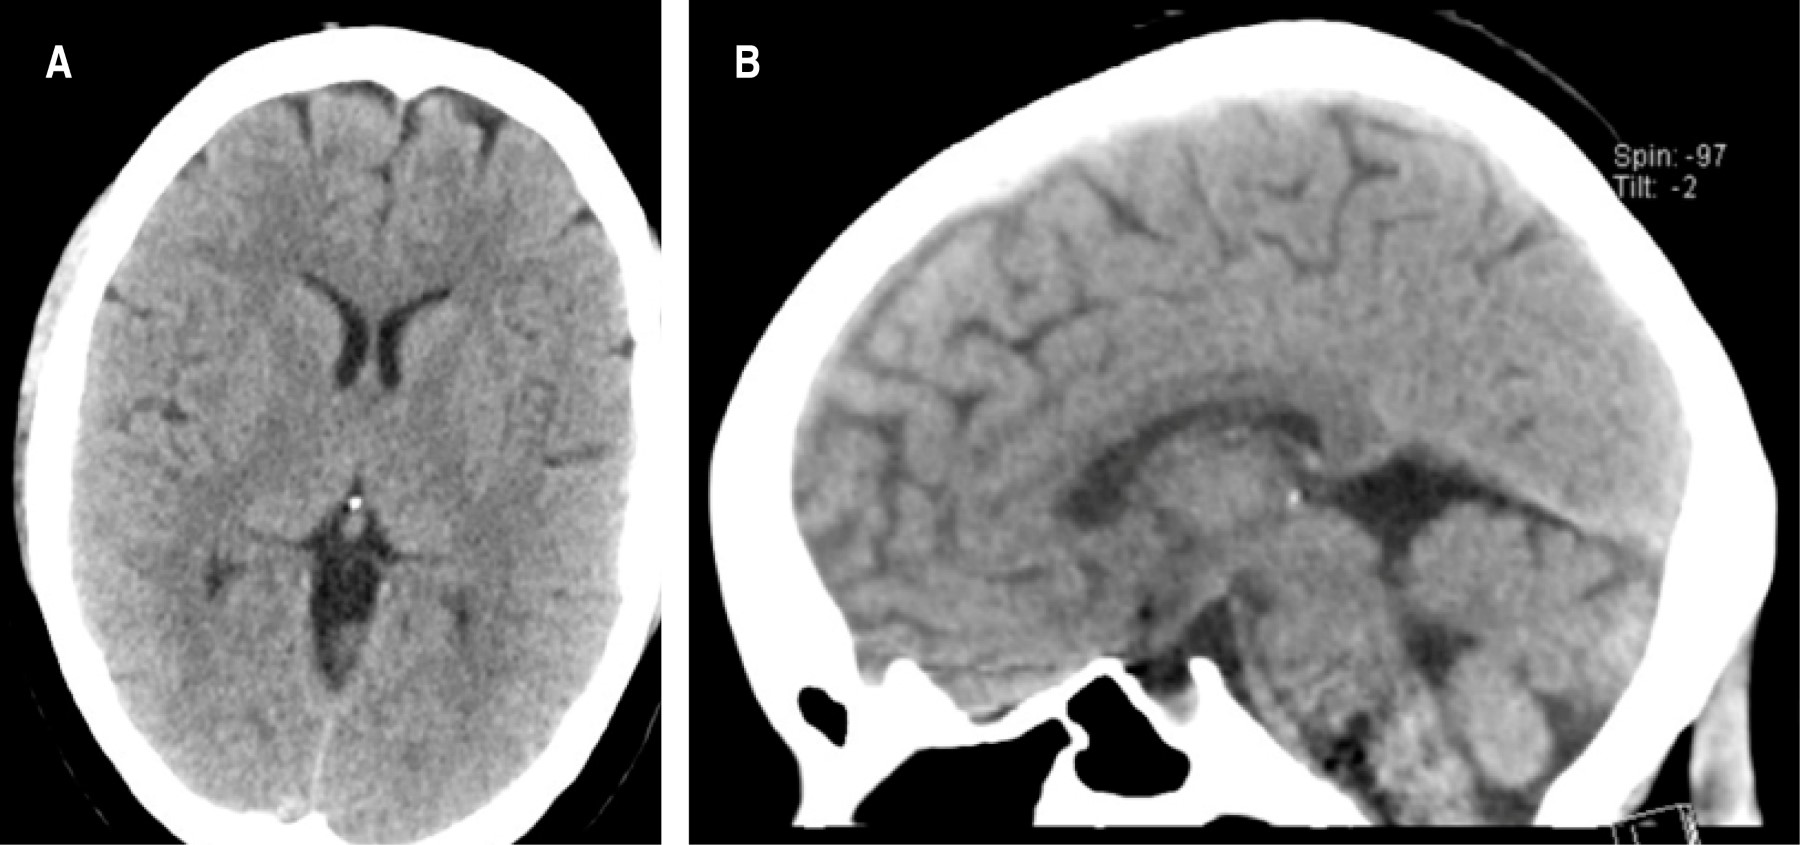

El NIHSS de ingreso fue de 14 puntos, la tomografía de cráneo simple inicial (Figura 2) mostraba un ASPECT 10/10, y una lesión neoplásica hipofisaria 5 × 6 mm sin sangrado intratumoral. La angiotomografía de vasos intracraneales evidenciaba una oclusión distal a la bifurcación de la arteria cerebral media (ACM) izquierda porción M3 (Figura 3). La glucometría de ingreso y sus signos vitales estaban dentro de límites normales.

Figura 3